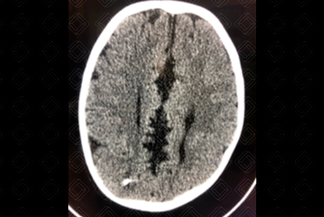

Descrição das imagens: Tomografia computadorizada do plano axial, exibindo a fossa posterior pequena e interdigitação da foice cerebral. Achados compatíveis com malformação de Chiari tipo 2. Observa-se ainda a presença de cateter de derivação ventricular na região parietal posterior esquerda.

• Tomografia computadorizada do crânio: Fossa posterior obliterada (pequena), incisura do tentório alargada, mesencéfalo em bico e deslocamento inferior do vérmis cerebelar;